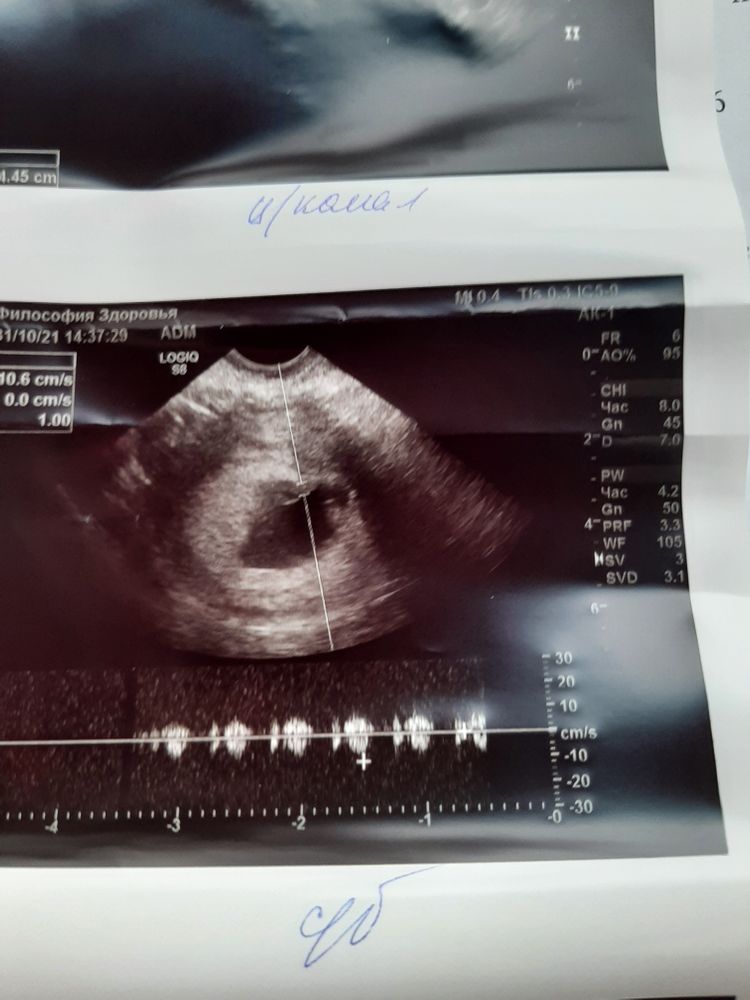

Ангелина, да, в заключении же написано 106 ударов

Света, я вижу. Доктор не сказал что мало?

Ангелина, нет...это мало?

Света, я спрашиваю просто. Просто у других как не посмотришь 130 минимум. И мне стало интересно. Но, если доктор ничего не сказал, значит все Ок